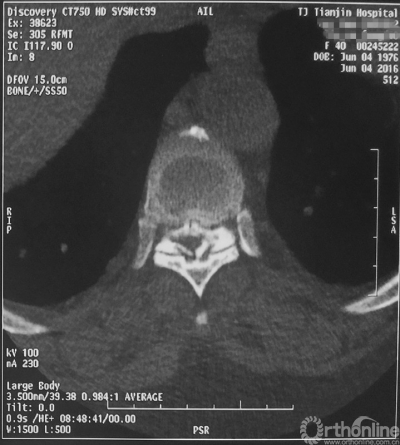

术前CT

家人曾带她辗转当地治疗,因病情复杂没有得到有效的治疗,于是慕名找到天津医院脊柱外科二病区主任苗军博士诊治,当苗军主任看到躺在担架上的刘女士痛苦的表情和渴望健康的眼神,他决定收她入院为其进行手术治疗。入院检查发现,刘女士患有多节段胸椎管狭窄症,以胸8-9节段严重,椎管狭窄达80%,脊髓已严重变性。